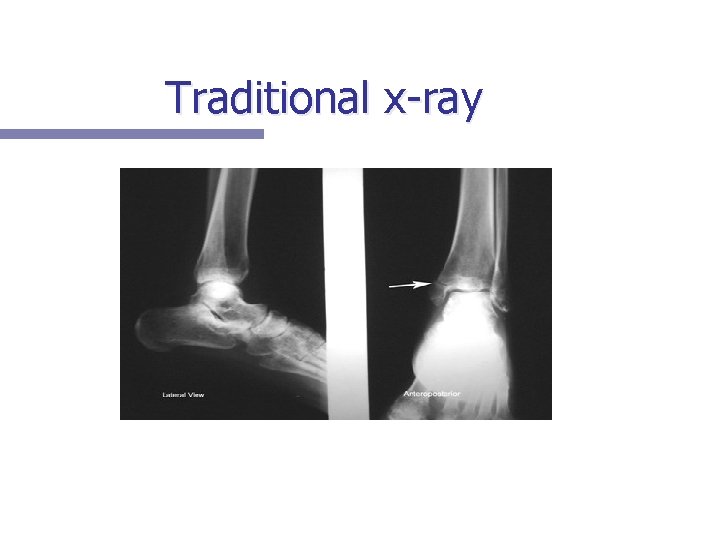

Traditional Xray n Definition: Beams of xrays, produced by an xray generator, transmitted through an object; ex: the part of the body to be scanned. The xrays are absorbed by the material they pass through in differentiating amounts, depending on the density and composition of the material. *Most likely used if a broken bone is suspected.

Traditional Xray n For example; bones absorb xrays relatively well, while soft tissue such as muscle fiber, which has a lower density than bone, absorbs fewer xrays. This results in a picture where the bones are white and tissue appears darker. This makes traditional xrays suitable for scans of bones and tissues dense in calcium, such as bone/teeth. Imaging technique done most frequently.

Traditional x-ray